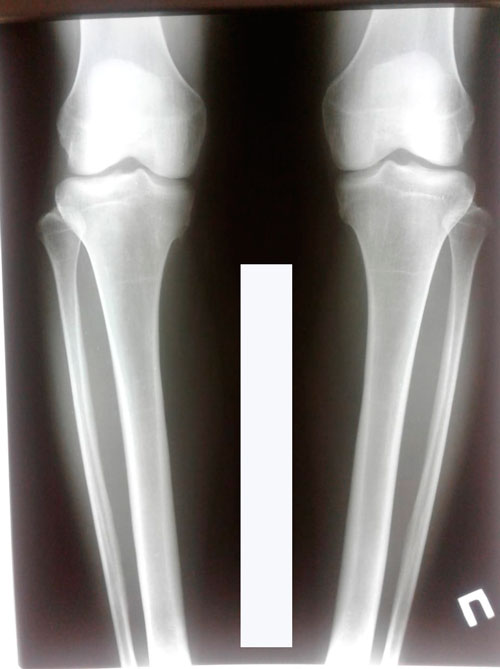

Дата снятия аппаратов 04.10.2018г.

Срок сращения 74 дня.